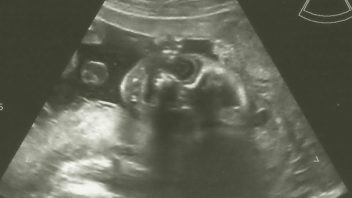

Denisa právě prožila 27. týden těhotenství. Chcete vědět, co se v tomto týdnu děje s vaším tělem?